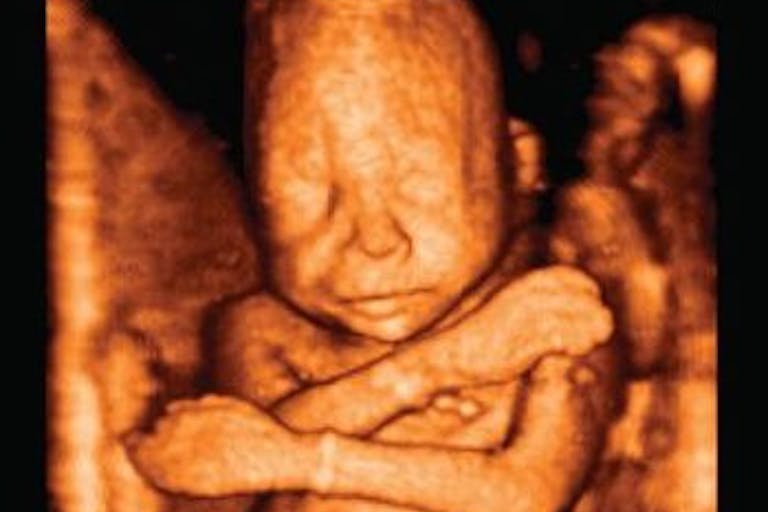

These women were aborting their preborn children (at ages in which the children could be considered viable) simply because they didn’t want to be pregnant. The common abortion procedure for this stage of pregnancy involves using a clamp to rip the child apart limb by limb as explained by former abortionist Dr. Anthony Levatino in this video: